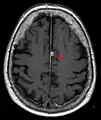

- T1-weighted (T1W) images: Cerebrospinal fluid is dark. T1-weighted images are useful for visualizing normal anatomy.

- T1 (note CSF is dark) with contrast (arrow pointing to meningioma of the falx)